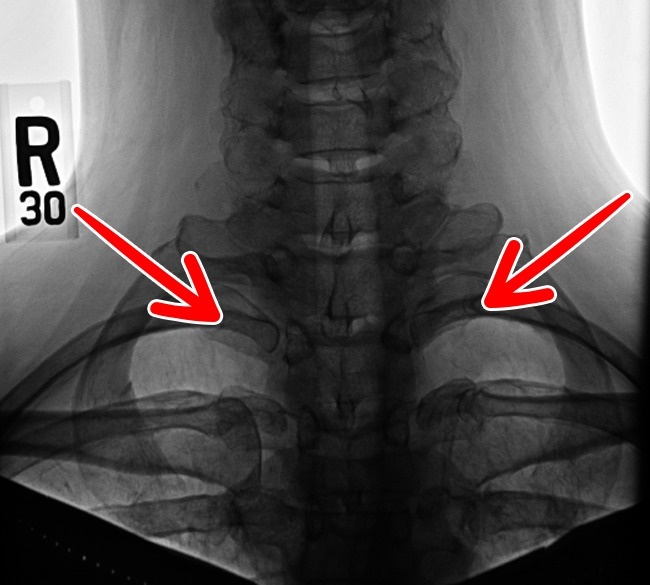

5. Neck rib

A set of cervical ribs, possibly a leftover from the age of reptiles, still appears in less than 1% of the population. Some people have it only on their left or right side, while some have both. They often cause nerve and artery problems.